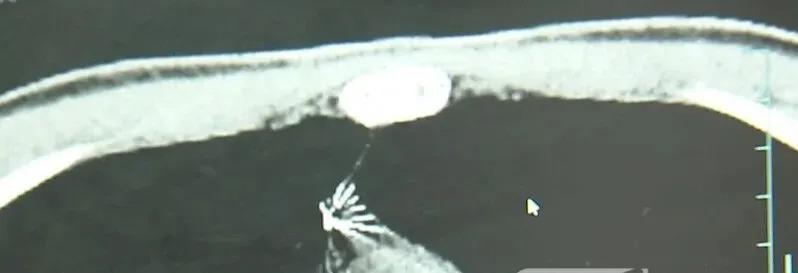

进一步的 CT 检查确认,异物是一枚金属针,斜插在肺组织内,位置十分凶险。

杭州市第一人民医院心胸外科副主任 冯兴:" 我们看到这个针的尖锐部,正好指向他体内的一个大血管,边上是上腔静脉和胸主动脉,因此这个针稍有不慎,就有可能造成周边血管的损伤,甚至危及生命。"